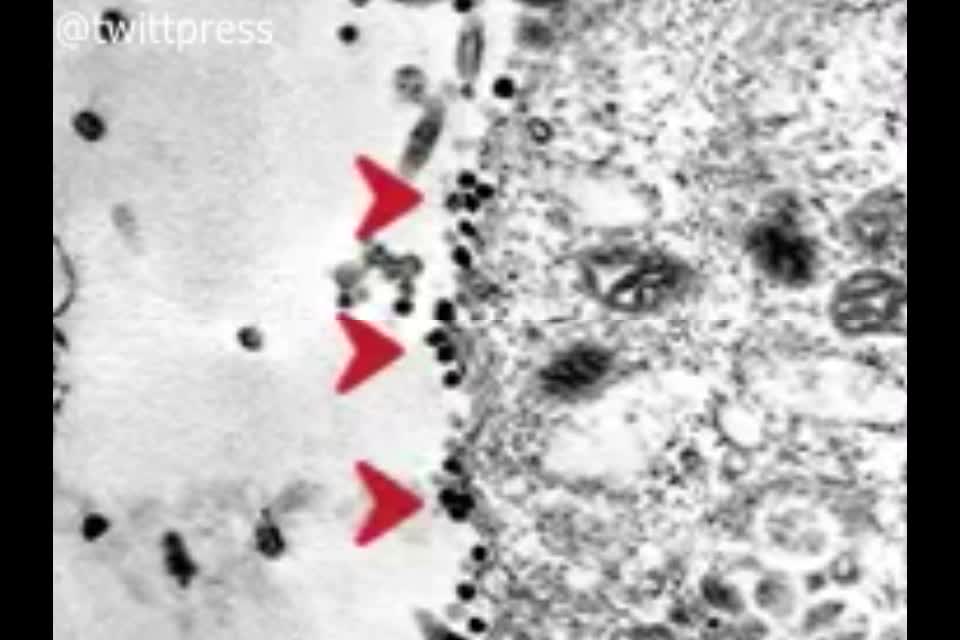

تصویر لحظه آلوده شدن سلول سالم به کرونا ضبط شد.